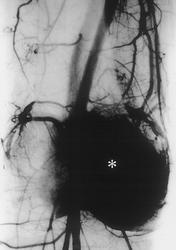

Злокачественная гигантоклеточная  опухоль возникает из доброкачественной (частота 10-20%). После операции возможно появление рецидива опухоли.

Гигантоклеточная опухоль